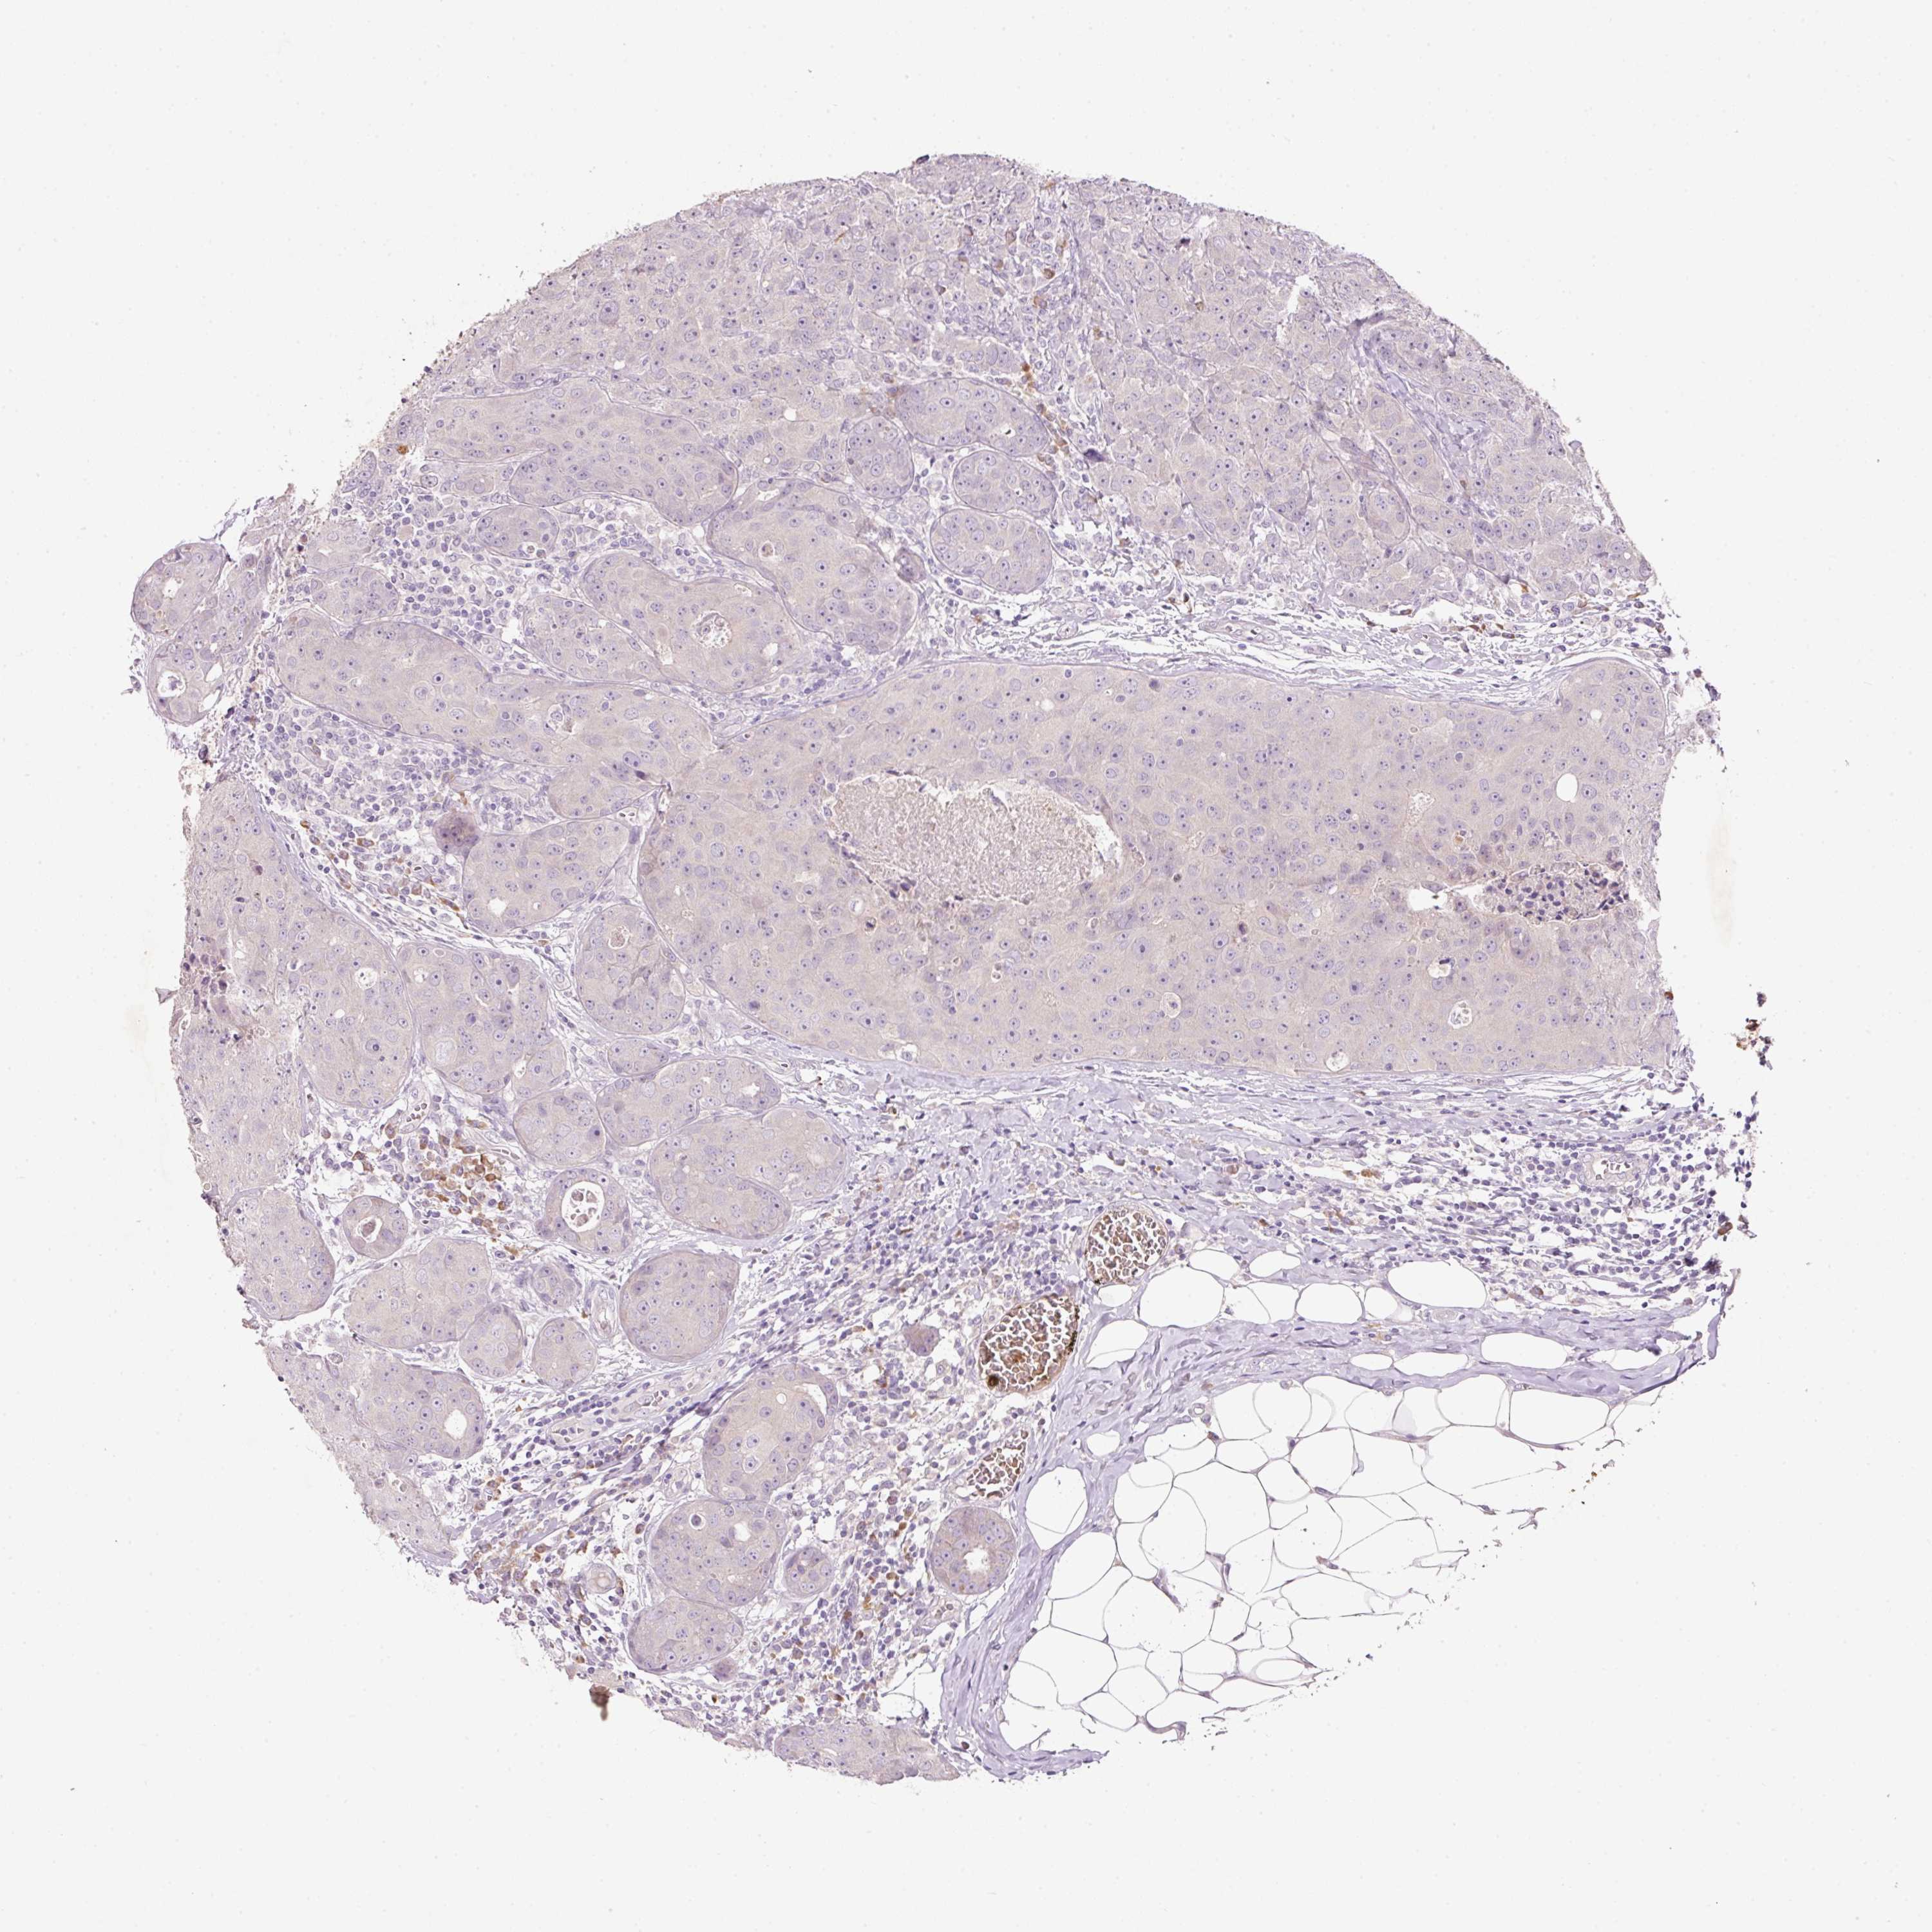

CANCER BREAST CANCER Show tissue menu

BRCA TCGA BRCA VALIDATION PROTEIN EXPRESSION

ANTIBODIES

AND

VALIDATION